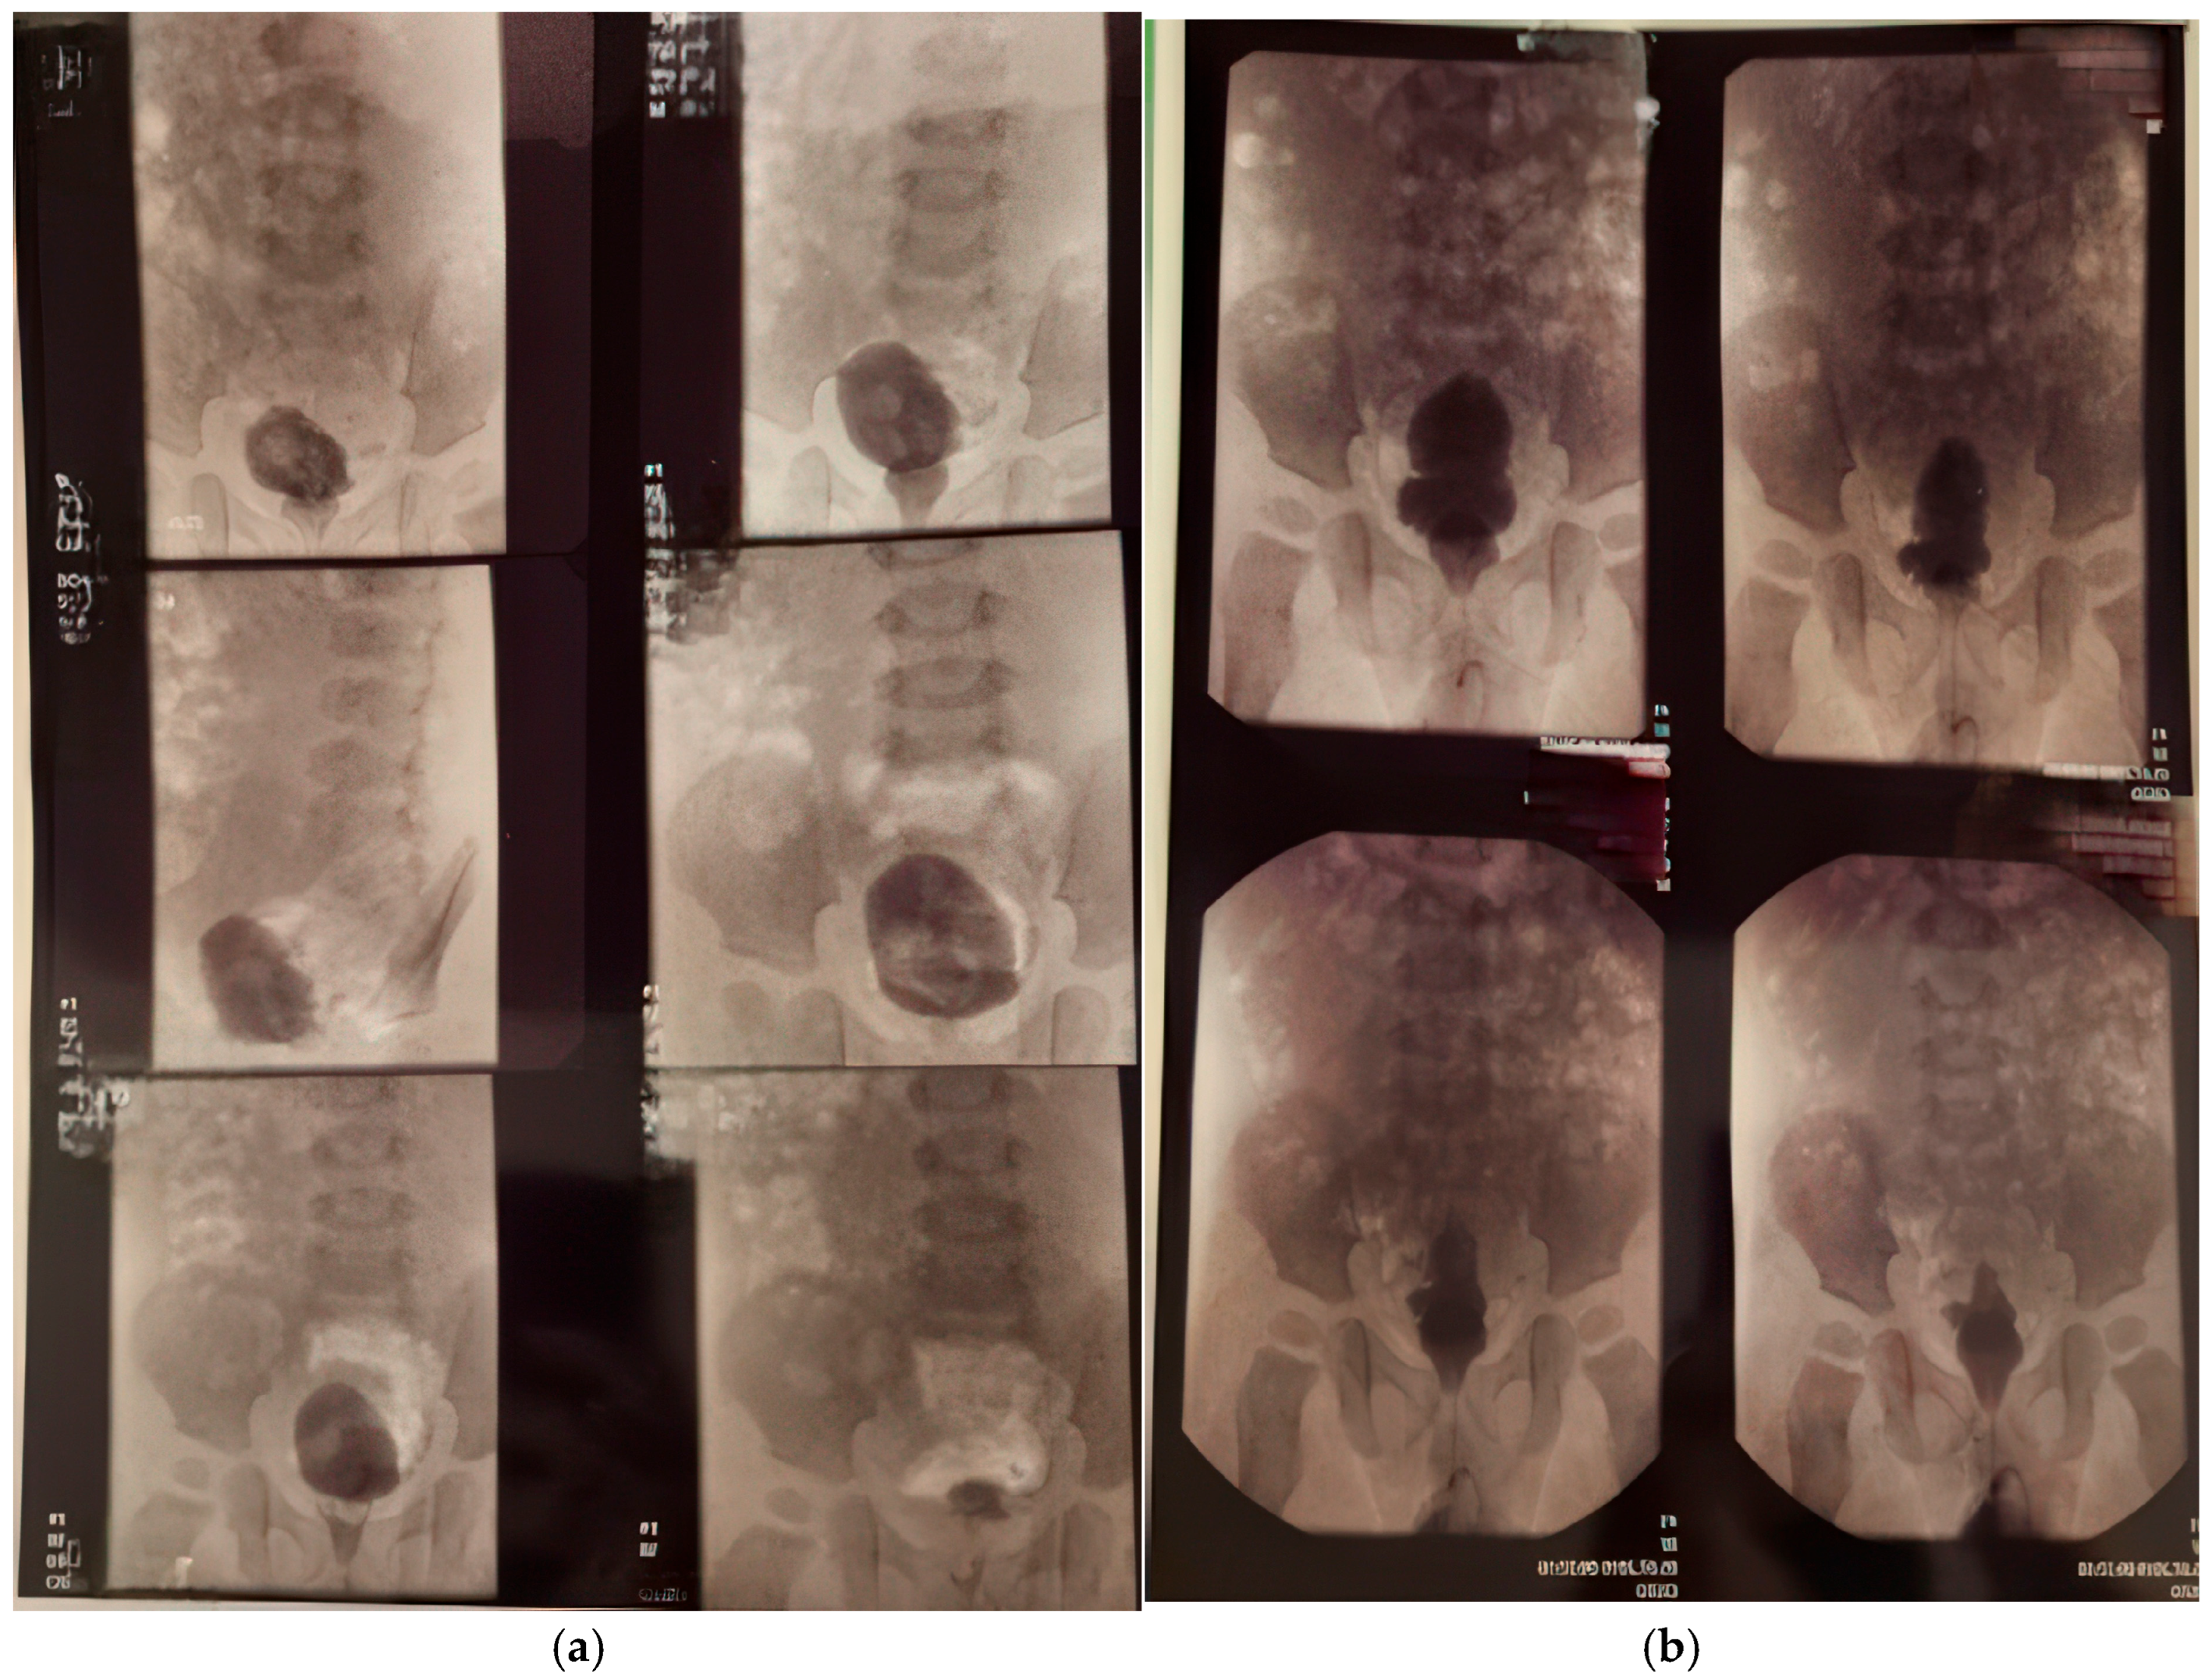

The last abdominal ultrasound performed at 7 years of life revealed that the right kidney, located in the renal fossa, appeared hypoplastic. It maintained a regular shape and contour and was mobile with respiration. Its dimensions were 6.7 × 2.4 cm, with a parenchymal index (PI) of 9 mm. The pyelocaliceal system of the right kidney showed mild distension in the upper calyceal group, and no calculi were present. In contrast, the left kidney, also situated in the renal fossa, displayed a regular shape and contour with good respiratory mobility. It measured 10.4 × 4.8 cm, with a PI of 11 mm at the upper pole. Notably, the pyelocaliceal system of the left kidney was dilated; the renal pelvis and calyceal groups measured approximately 3.3 × 3 cm, and no calculi were observed. The left ureter was clearly visible at the renal hilum, measuring approximately 11 mm in diameter. The urinary bladder contained anechoic fluid and exhibited thickened walls. The left ureter could be visualized in its lower third, measuring about 8 mm in diameter, while the right ureter was seen at its entry into the bladder. The initial conclusions drawn from this ultrasound included grade III/IV hydronephrosis of the left kidney, a hypoplastic right kidney, and a status post complete repair of pyeloureteral duplication. The final conclusions further clarified that the right kidney demonstrated grade I hydronephrosis, the left kidney showed grade III/IV hydronephrosis, and there was evidence of a neurogenic bladder, all in the context of a previously completed repair of pyeloureteral duplication on the right side (Figure 8).

Figure 8.

Renal ultrasound: (a) hypoplastic right kidney; (b) pelvicalyceal dilation of the left kidney; (c) dilated renal pelvis and ureter on the left kidney; (d) bladder with a modified (“funnel-shaped”) appearance; (e) pelvic dilation of the left kidney; (f) ureter dilated at the hilum of the left kidney.